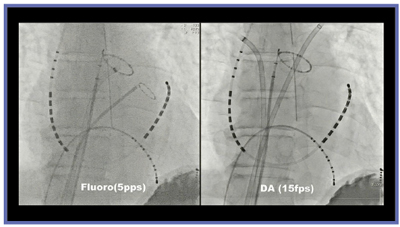

アブレーションの透視時間と入射線量の関係を見ると,パルスレートの低減やPureBrainにより,線量を大幅に低減することができ(図1),撮影の画質と比較しても低線量透視の画質は遜色なく,デバイスは十分な視認性を得ることができる(図2)。

図2 低線量透視と撮影の画質比較

PureBrainで提供される低線量透視モードと撮影と 比較してもデバイスは十分な視認性が得られている。